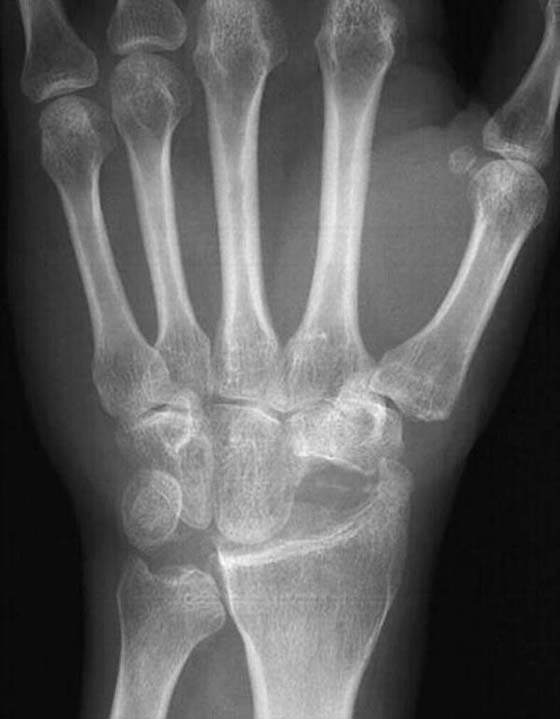

Proximal-Row Carpectomy

First described by Stamm in 1944,30 PRC attempts to convert a complex link articulation in the wrist to a simple hinge joint. Imbriglia and colleagues31 demonstrated that the motion is not that of a hinge joint; rather, the motion between the capitate and radius is rotational and translational with a moving center of rotation.

The procedure is indicated for disease affecting the proximal carpal row, including scaphoid nonunion, radioscaphoid arthritis, scapholunate instability, and AVN of the lunate or scaphoid. It is contraindicated if degeneration is present and involves the capitate or lunate facet of the radius. The theoretical advantage of the PRC over arthrodesis includes increased motion, decreased period of immobilization, elimination of internal fixation, bone grafting, and potential nonunion.

The surgical approach is dorsal, with removal of the scaphoid, lunate, and triquetrum (Fig. 76-9). Care is taken to preserve the radioscaphocapitate ligament to prevent instability. The dorsal capsule is imbricated and reattached to the dorsal radius.

images

Figure 76-9 Proximal-row carpectomy.

Several authors23,31-33 demonstrated good short- and long-term results with PRC. The average wrist flexion–extension arc was 70 to 80 degrees with 8 degrees of radial deviation and 19 degrees of ulnar deviation. The grip strength averaged 71% to 79% of that of the opposite wrist. Cohen and Kozin23 found no difference in the results of a PRC compared with a four-bone fusion.